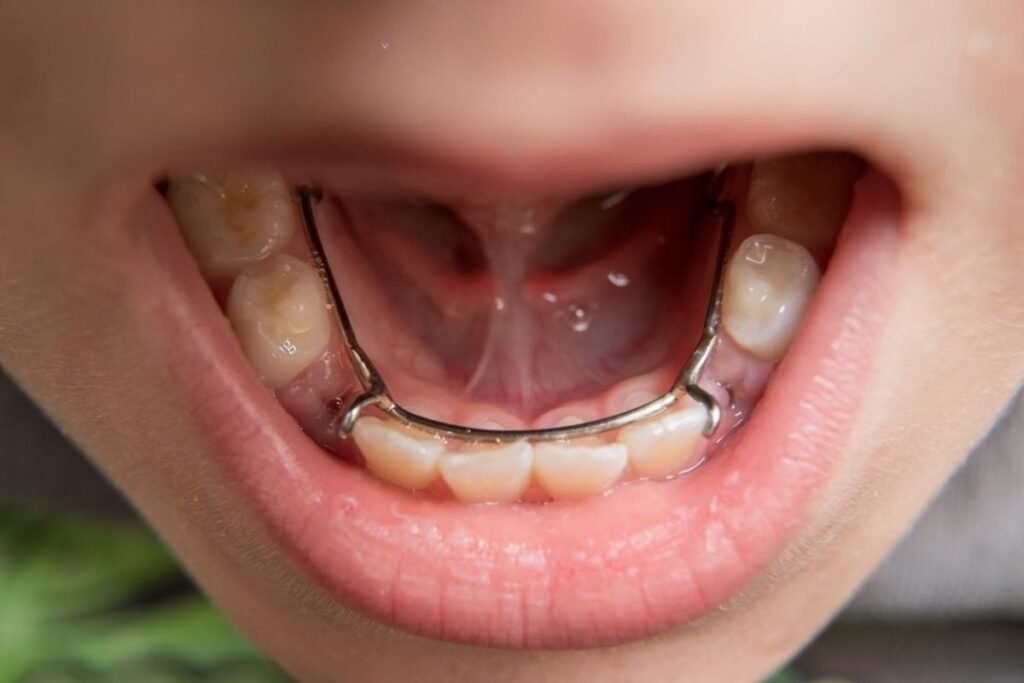

- En cas d’extraction précoce, envisager un mainteneur d’espace : fil soudé, arc lingual, arc de Nance, arc palatin, ou prothèse pédiatrique.

- Conservation du Lee Way : Utilisation de lip bumper, arc lingual, arc palatin de Nance, ou arc transpalatin pour stabiliser les molaires.

- Endognathie : Disjonction (disjoncteur).

- Endoalvéolie : Expansion (plaque avec vérin médian, quad hélix).

Endoclusion postérieure unilatérale

- Endoalvéolie : Expansion (plaque avec vérin médian, quad hélix avec/sans surélévations).

- Sans latérodéviation : Expansion asymétrique (plaque avec vérin médian et volet, quad hélix, TIM croisées).